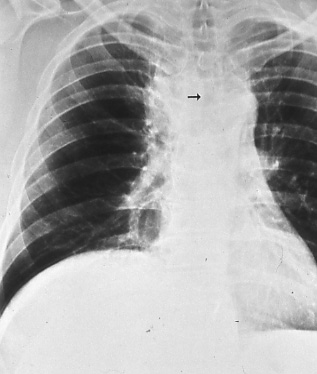

Fig. 47: Posterior-anterior chest radiograph shows a large mass in the right paratracheal region. The trachea is deviated to the left by the mass (black arrow) in keeping with T4, stage IIIB disease. Elevated right hemidiaphragm suggests phrenic nerve involvement.